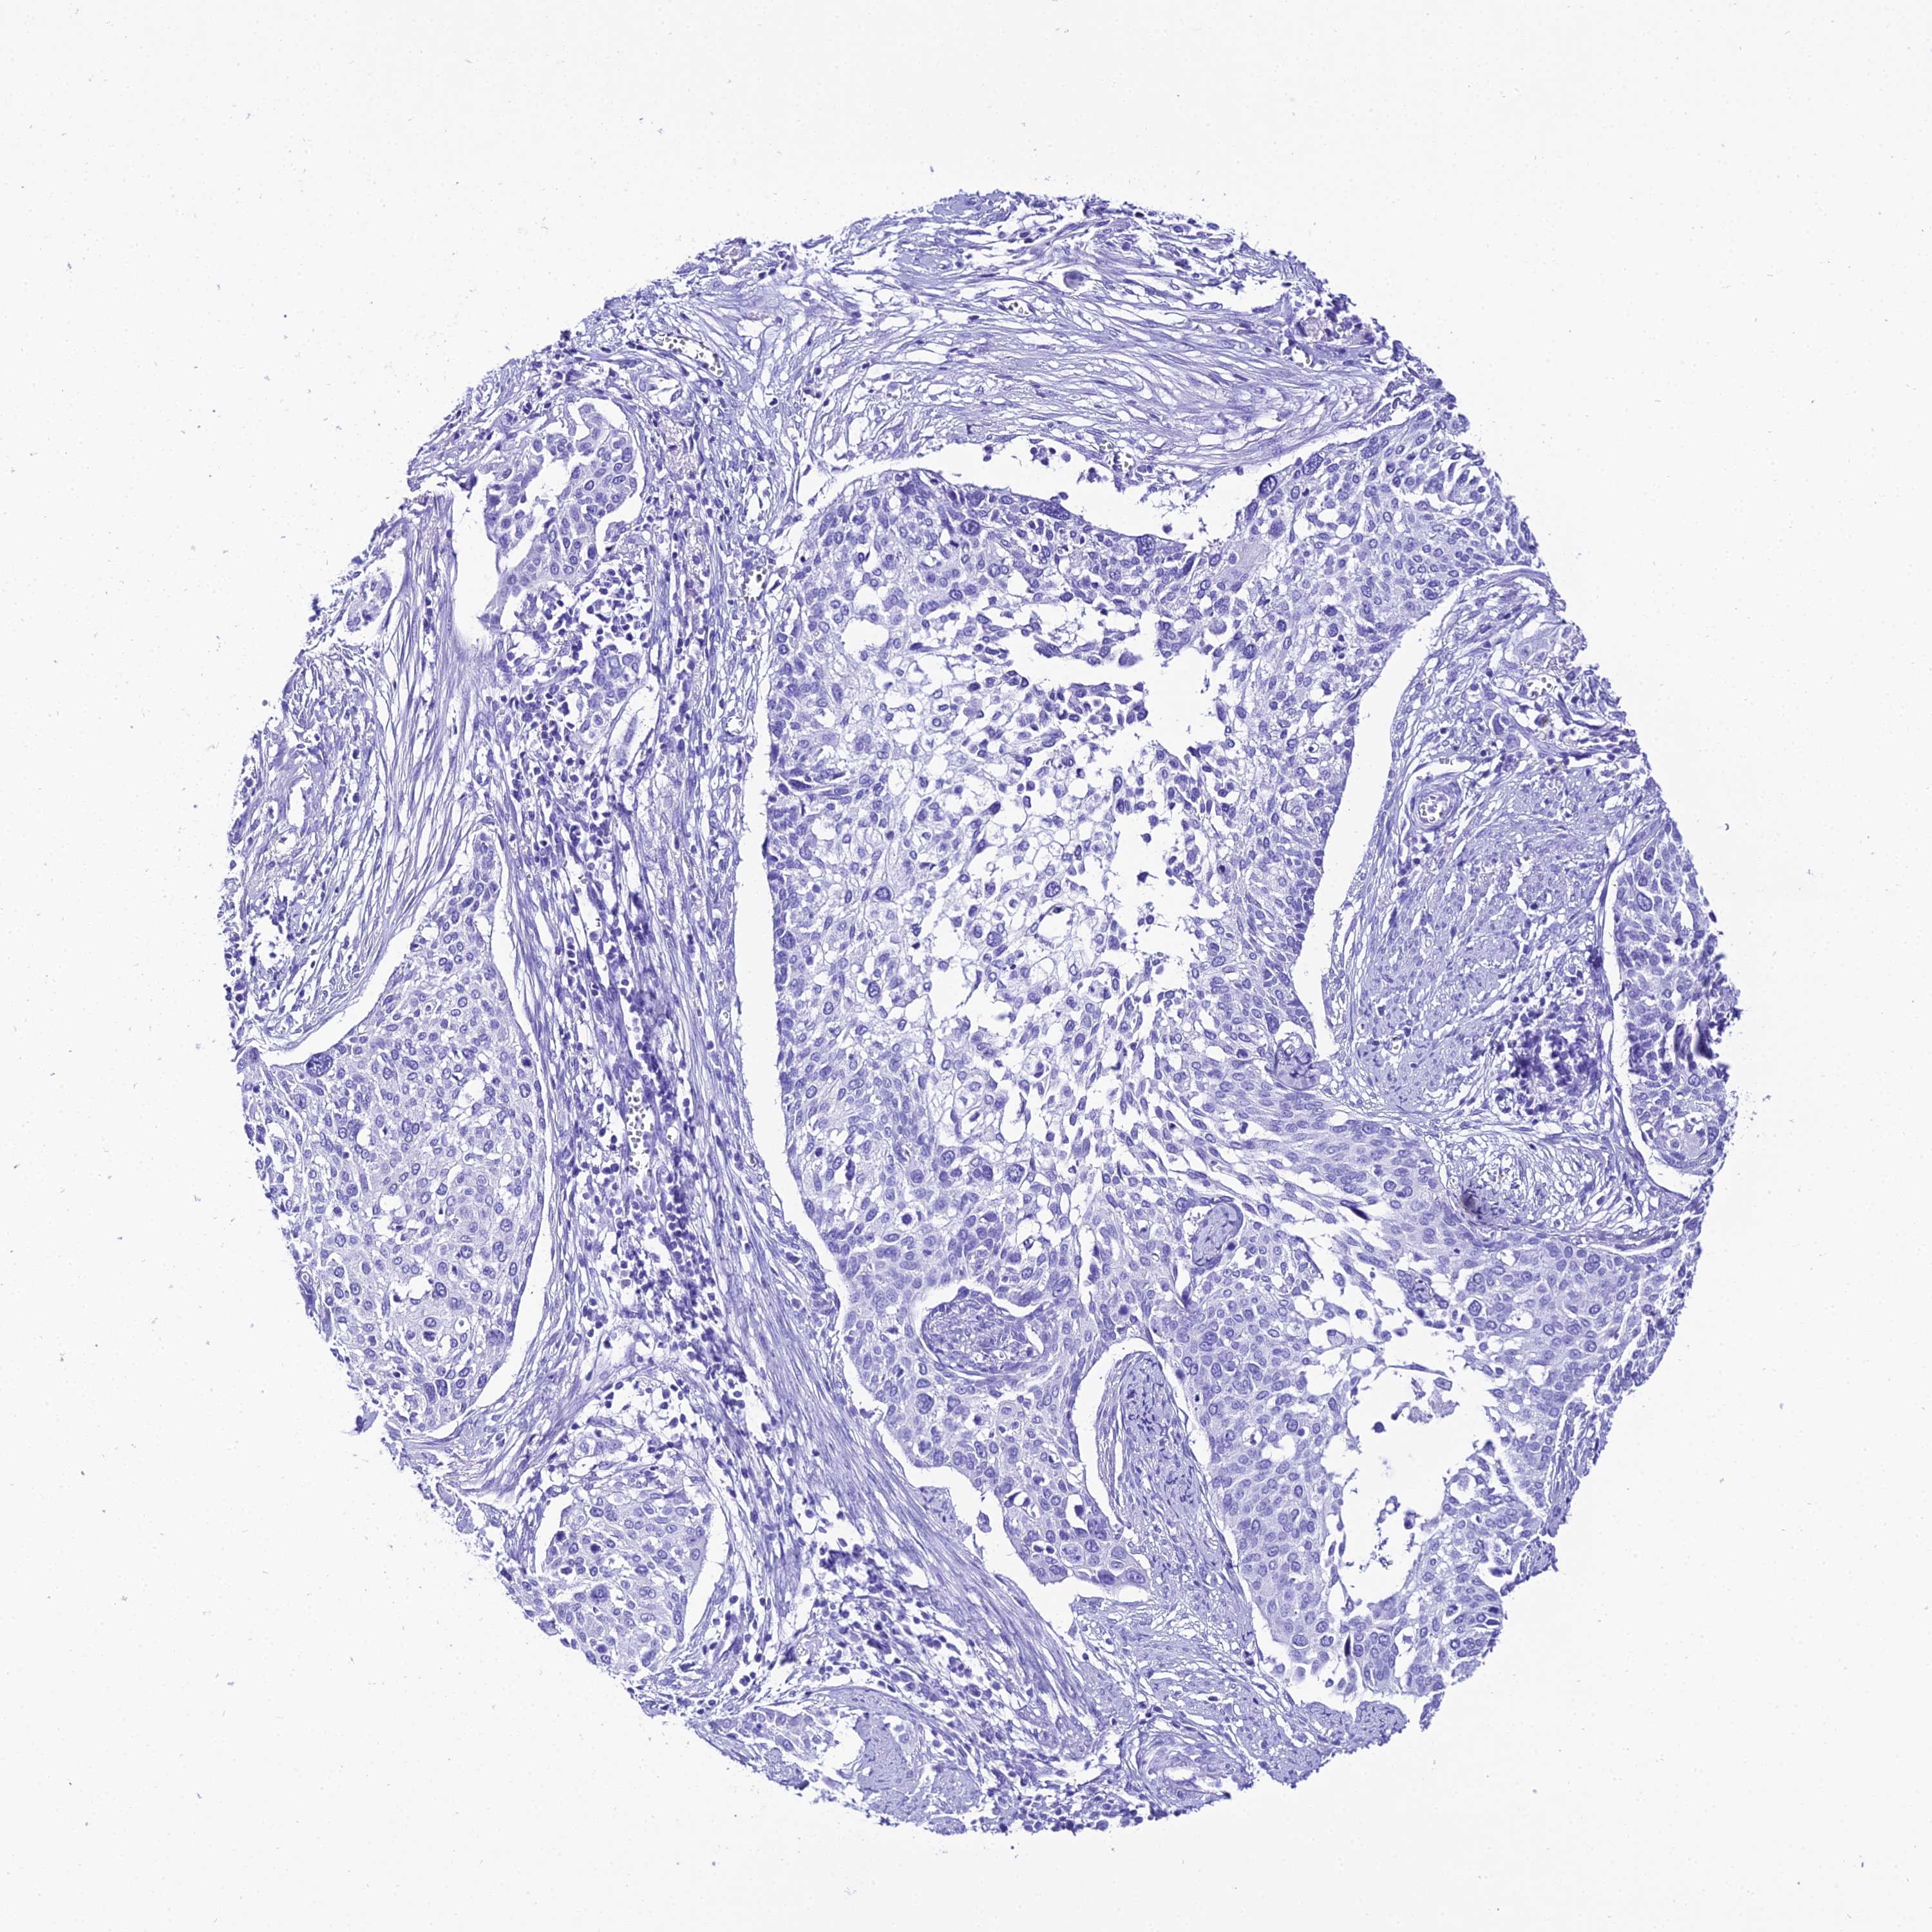

CERVICAL CANCER - Protein expressioni

A mouse-over function shows sample information and annotation data. Click on an image to view it in a full screen mode. Samples can be filtered based on level of antibody staining by selecting one or several of the following categories: high, medium, low and not detected. The assay and annotation is described here.

Note that samples used for immunohistochemistry by the Human Protein Atlas do not correspond to samples in the TCGA dataset.

Antibody stainingi

Antibody staining in the annotated cell types in the current human tissue is reported as not detected, low, medium, or high, based on conventional immunohistochemistry profiling in selected tissues. This score is based on the combination of the staining intensity and fraction of stained cells.

Each image is clickable and will lead to virtual microscopy that enables deeper exploration of all samples and also displays staining intensity scores, fraction scores and subcellular localization as well as patient and tissue information for each sample.

Antibody HPA045461

Staining

High

Medium

Low

Not detected

Intensity

Strong

Moderate

Weak

Negative

Quantity

>75%

75%-25%

<25%

None

Location

Nuclear

Cytoplasmic/membranous

Cytoplasmic/membranous,nuclear

Squamous cell carcinoma, NOS

Adenocarcinoma, NOS